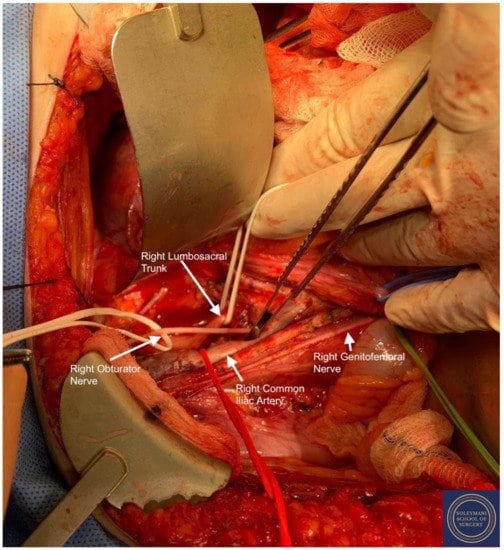

- The pararectal spaces were developed with exposure and preservation of the hypogastric nerves adhering medially to the mesorectum up to the level of the inferior hypogastric plexus and vein aergentis. The external iliac and obturator lymph nodes of the anterior pelvic compartments (Figure 6) were removed by completely stripping the external iliac artery and vein and removing the paravisceral pelvic fat pads, obtaining exposure of the obturator nerve, obturator artery and vein, the arcus tendineus, and proximal sciatic nerve (Figure 7 and Figure 8).

- -

- Pelvic lymph node dissection was continued in the posterior compartment by removing all lymph nodes and fatty tissue around the internal and common iliac vessels, exposing the proximal pelvic obturator nerves and the lumbar rami of the sacral plexus. Para-aortic lymph node dissection was subsequently completed up to the level of the renal veins.